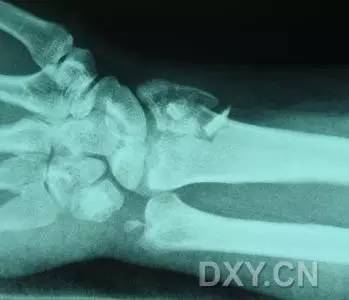

2. Colles 骨折

桡骨远端骨折,伴有桡骨远端向背侧的移位,可以有或没有尺骨干的骨折。具有这几个特征:背侧粉碎、向背侧成角、向背侧移位且挠骨短缩的关节外骨折。

典型 colles 骨折,枪刺样、餐叉样畸形